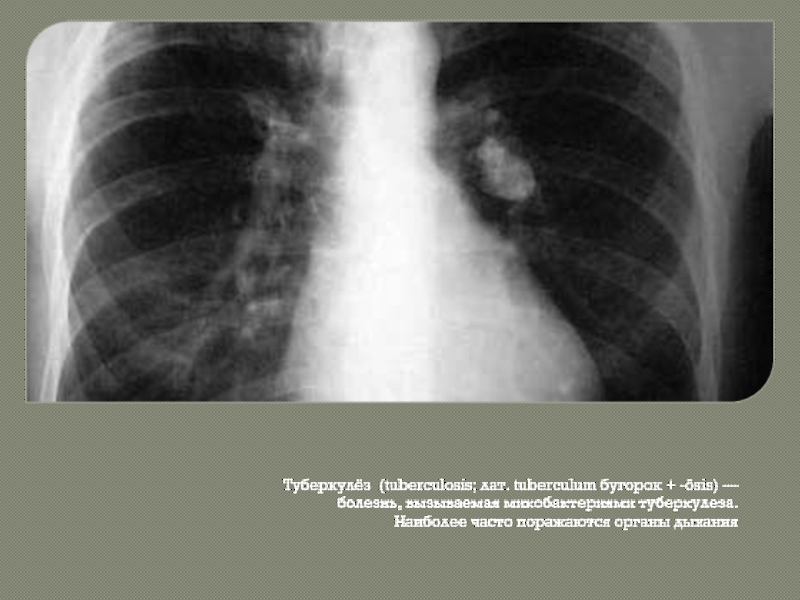

Симптомы и признаки туберкулеза: как распознать заболевание

Раздел: Визуальные уроки